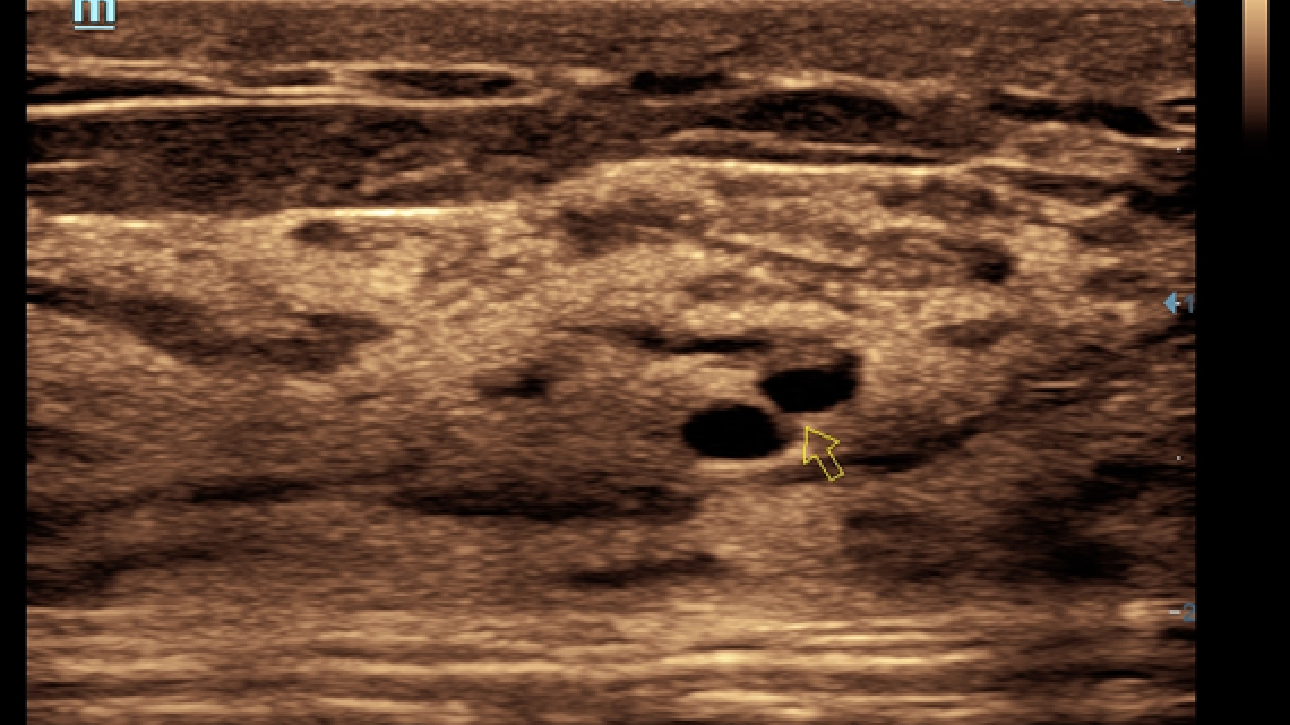

Obrazy kliniczne